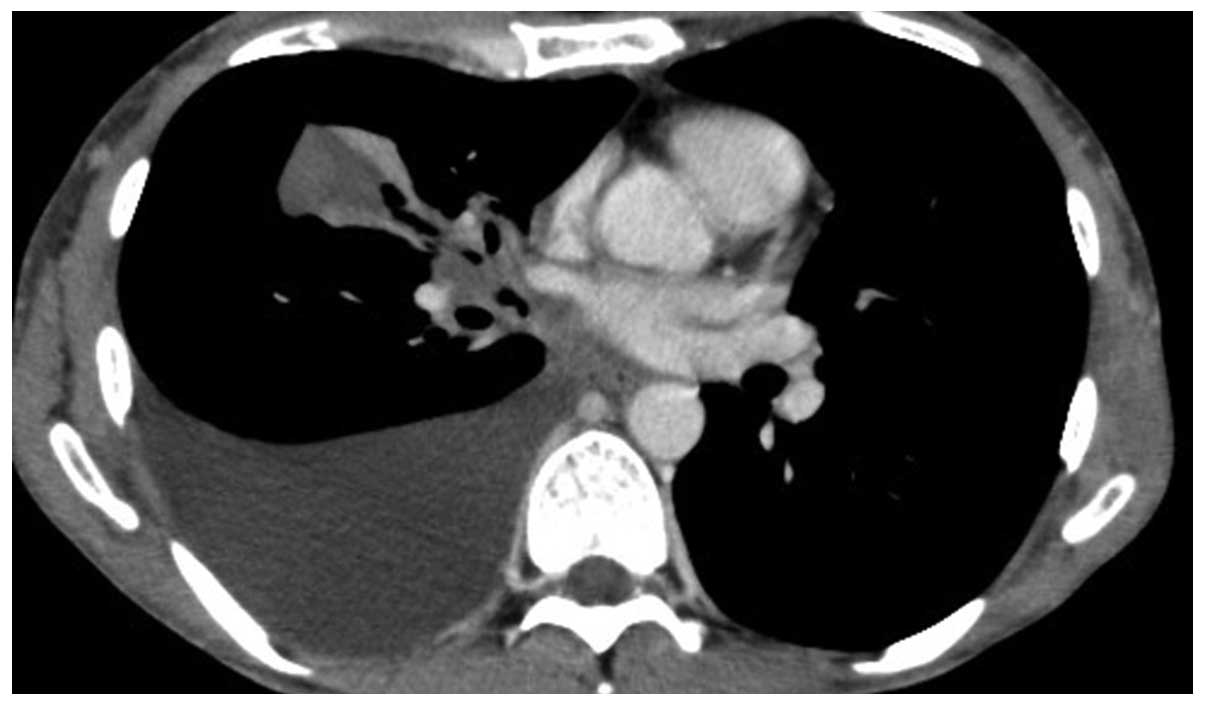

As fluorescence in situ hybridization revealed a translocation of ALK, the patient received crizotinib therapy. After one month, the physical examination and chest CT revealed a significant decrease in the maximum aggregate tumor measurement. The tumor response was classified as PR, but the treatment was discontinued due to crizotinib-related grade 3 general fatigue, according to the National Cancer Institute-Common Toxicity Criteria, version 2.0. The patient declined additional treatment and all the lesions, including the primary site and cervical, axillar, mediastinal and abdominal lymph node metastases, increased in size. A chest CT scan revealed a large mass with a massive pleural effusion (Fig. 1). One year after the discontinuation of crizotinib, the patient consented to receiving alectinib. After 2 weeks of alectinib treatment, a chest CT revealed a significant decrease in the maximum aggregate tumor measurement (Fig. 2). The tumor response according to the RECIST guidelines was classified as PR. Adverse events, including general fatigue, were not observed. At 4 weeks after the initiation of alectinib, the patient remained alive and adverse event-free.

Figure 1.

Chest computed tomography (CT) scan showing a large mass with a massive pleural effusion.